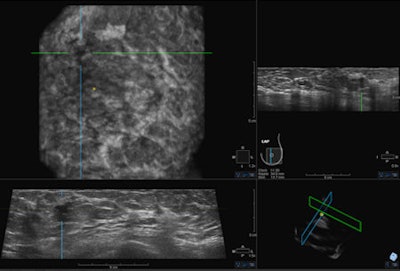

The European Asymptomatic Screening Study (EASY) investigated the effectiveness of the somo-v ABUS system by assessing cancer recall, biopsy, and detection rates for the combination of full-field digital mammography (FFDM) and ABUS, compared with mammography alone. It was led by Dr. Karin Leifland, PhD, head of the Unilabs mammography department at Capio St Göran's Hospital in Stockholm.

The somo-v ABUS system was specifically designed not only for screening dense breast tissue, but also to operate efficiently in the screening environment. Being automated in nature, the device is operator independent and is associated with enhanced consistency, and the radiologist only needs to interpret the images rather than necessarily conducting the scan, aiding workflow, and managing time efficiency, she explained.

All women received a mammogram and an ABUS screen. The first radiologist read the mammogram, blinded to the ABUS, and then read the ABUS later. A second radiologist also read the mammogram study to confirm the findings, so effectively there was a double reading.